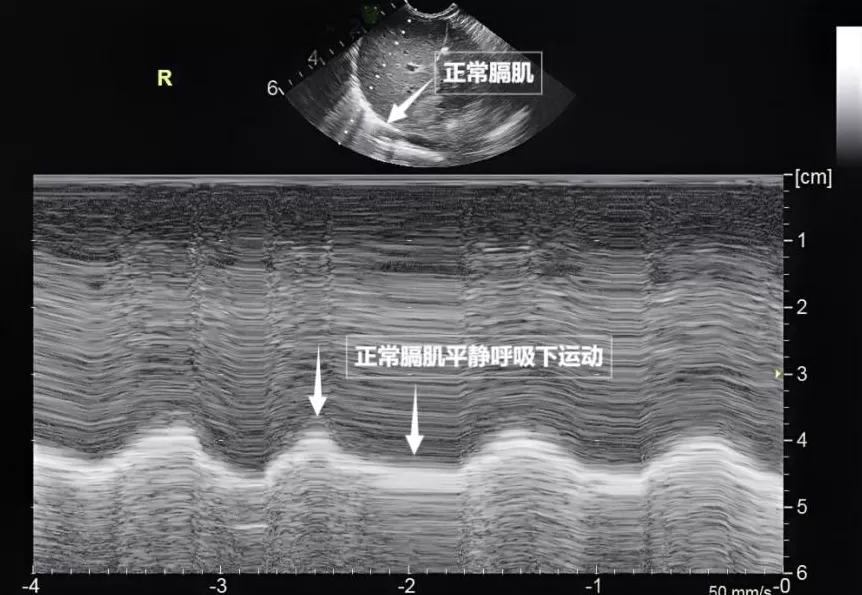

第三景:" 呼吸的动力泵 " 的协同作战——呼吸肌肉

呼吸看似简单,实则是多组肌肉精密配合的 " 团体操 "。肺部超声不仅能观察肺的形态,更能通过实时动态影像," 捕捉 " 这些呼吸肌的活动状态,为评估呼吸功能提供独特视角。膈肌是呼吸肌的 " 总指挥 ",位于胸腔与腹腔之间。平静呼吸时,膈肌收缩下沉,胸腔容积扩大,空气自然吸入;舒张时,膈肌回升,肺部弹性回缩完成呼气。超声下可见膈肌呈光滑弧形,随呼吸规律上下移动(见下图)。肋间外肌则是 " 肋间隙的升降机 ",收缩时上提肋骨,扩大胸腔前后径,辅助吸气。这对 " 黄金搭档 " 承担了日常呼吸 70% 以上的工作量,是维持呼吸的 " 主力军 "。

图为正常膈肌超声表现